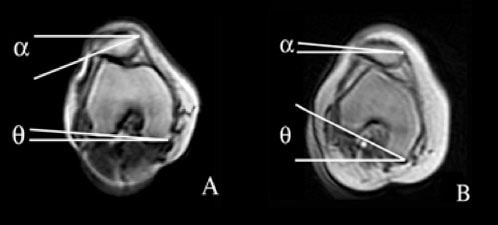

During weight-bearing, the femur moves about a fixed patella. Thus, excessive femoral IR localizes contact primarily to the lateral facet of the patella (Powers et al). In fact, just 10 of IR can substantially decrease the PFJ contract area and increase joint stress by 50%.The figure below demonstrates the lateral tilt of the patella during non-weight bearing (A) and the femoral IR altering the contact area during weight bearing (B).

[caption id="attachment_1310" align="aligncenter" width="498"] (A) lateral tilt of the patella during non-weight bearing; (B) femoral IR altering the contact area during weight-bearing.[/caption]